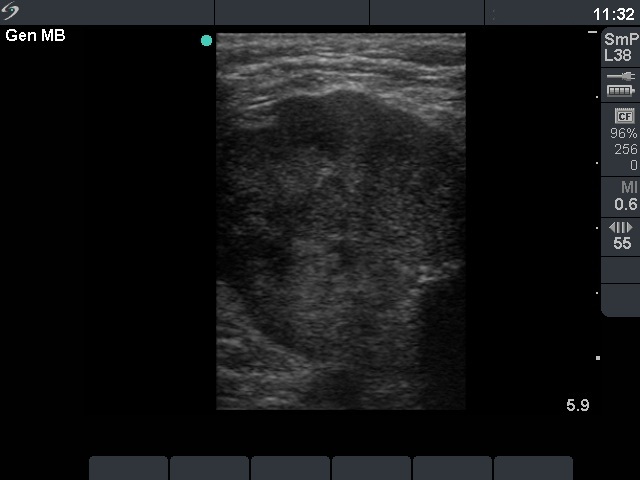

Ultrasonography: there was a hypoechogenic, inhomogeneous nodule occupying almost the entire left thyroid. The nodule spread substernal. The lesion contained microcalcifications and had irregular borders. The intranodular blood flow was decreased.